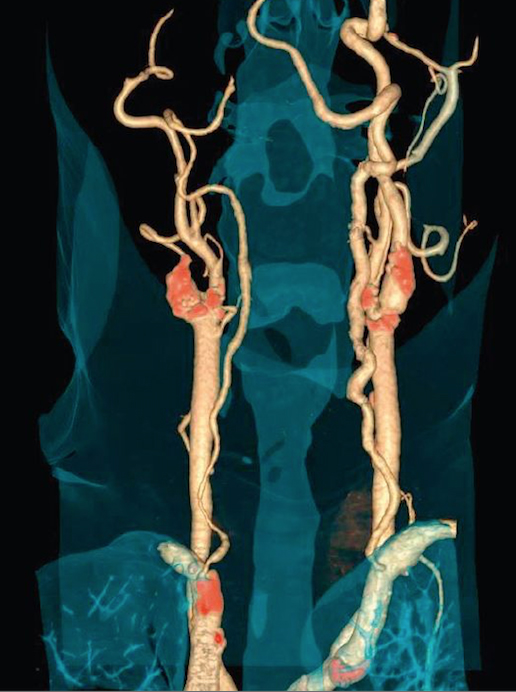

To je metoda prikaza malih arterija koje hrane  srčani mišić, upotrebom CT skenera, koji prikazuje protok krvi u koronarnim arterijama i kompjuterskog softvera da bi se dobio odgovarajući trodimenzionalni prikaz. CT angiografija je neinvazivni način da se prikažu zidovi koronarnih arterija I nadju eventualni aterosklerotski plakovi, što pomaže liječniku u odredjivanju rizika srčanog udara.